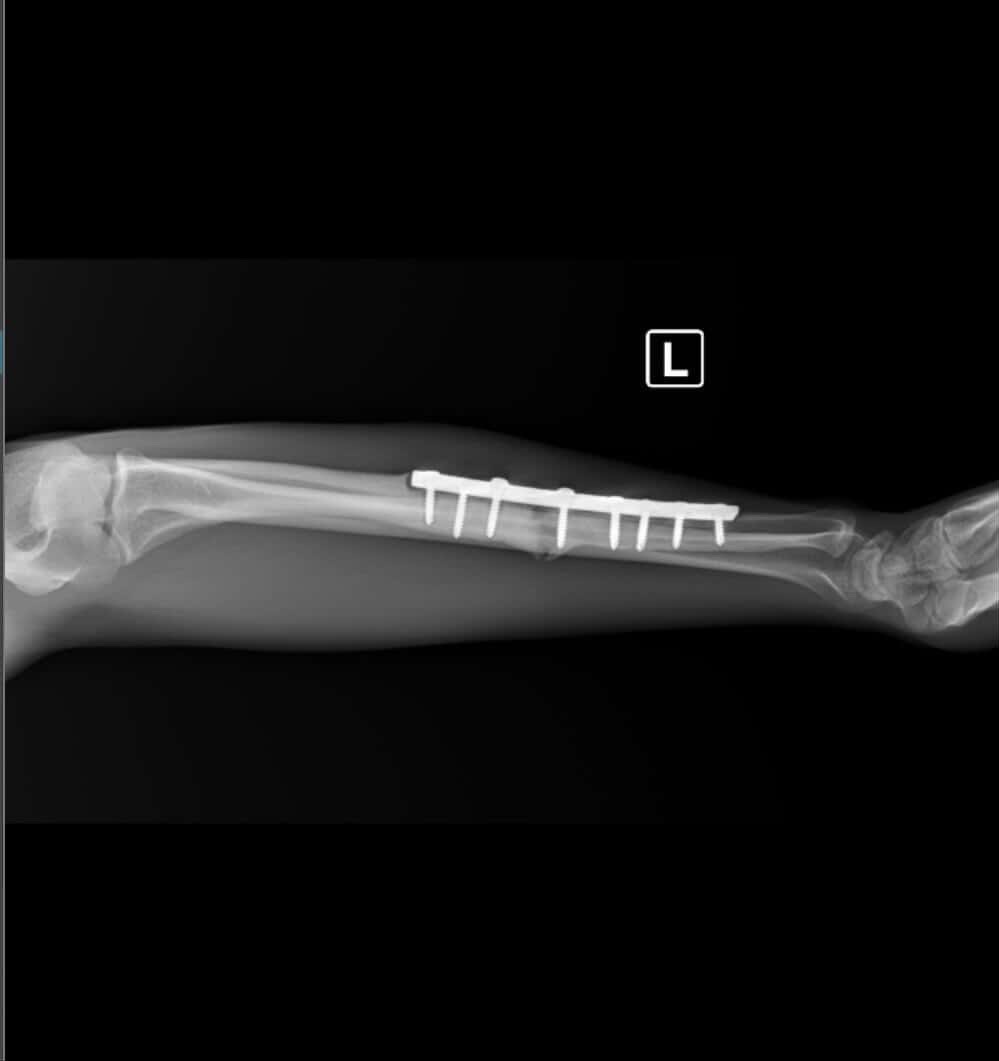

He’s not just dedicated, he’s proven. Axel built an undefeated amateur record of 27-0 and has continued his success as a professional with an impressive 19-6 record. He was in preparation for what would have been his second professional world title opportunity when he suffered a fractured arm during training.

Now, Axel needs surgery to properly heal and continue his career. Doctors are optimistic that with timely surgery and recovery, he can be back to fighting as soon as November of this year.